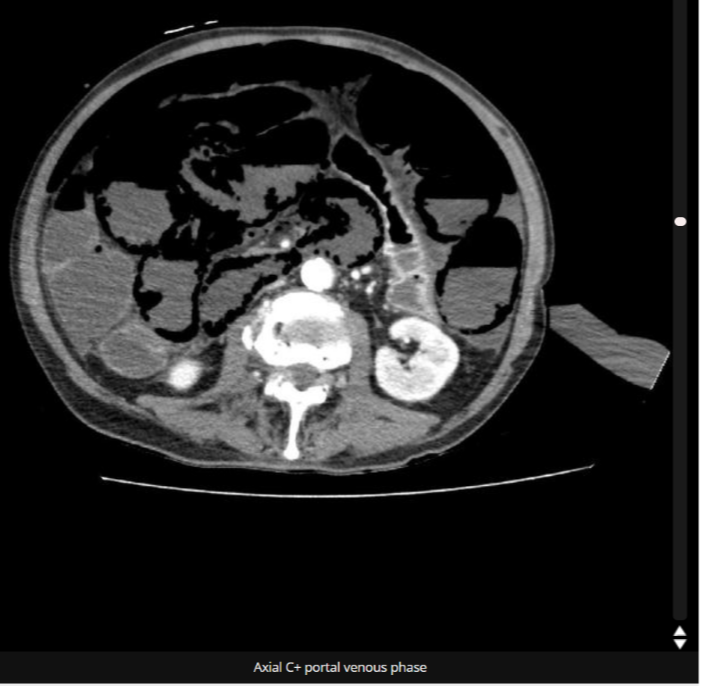

전일부터 마른 기침정도하는 발열 및 General weakness 로 내원했는데 covid pcr 음성에 Crp 2점대에 acidosis 없는 BST 600 측정되어 발열 focus 찾기위해 가슴이랑 복부 CT 찍어놓고, axial view만 눈대중으로 쑥 훑고 폐 조금 지저분한거 말고 모르겠는데 하고 정규시간이라 영상의학과에 판독 받아보니 small bowel에 약 15cm 정도 pneumatosis intestinalis로 판독 나옴

다시 한번 부족한 내 판독 능력으로 하나라도 안놓치려면 coronal view도 꼭 보고 머리속에 pneumatosis intestinalis 도 배제질환으로 넣어두고 bowel wall도 안놓치고 최대한 다보게 노력하자

Uptodate에 수술 indication 찾아보니 내 환자의 경우 lactic acidosis 도 없고, 복부 PE에서도 특이 이상소견 없고 portal vein은 intact 한 상태로 수술 indication은 아니었으나